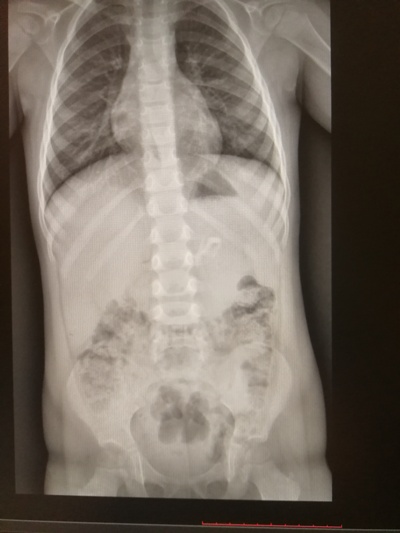

Подозрение на инородное тело желудочно-кишечного тракта.

При выполнении обзорной рентгенограммы органов грудной клетки, брюшной полости и забрюшинного пространства в проекции желудка определяется включение средней интенсивности, неоднородной структуры, неправильной формы.

При внимательном изучении рентгенологического снимка становится ясно, что инородное тело не что иное, как...

... туфелька её куклы!!